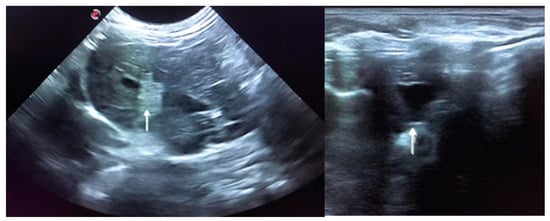

Ultrasound revealed a slightly heterogeneous liver with a hypoechoic caudate lobe and a kidney stone considered meaningless for this case. There were no obvious signs of vascular compromise. However, shaving the abdomen for the ultrasound exam revealed a large haematoma that extended from the neck to forelimbs, thorax and upper-half of the abdomen. This was assumed to have originated from the jugular blood collection carried out in the previous day, despite the seemingly atraumatic puncture.

In June 2020, the rabbit was readmitted due to anorexia, lethargy, coprostasis and abdominal discomfort. The rabbit had lost 80 g, weighting then 1420 g, and for the first time, mildly hyperthermia (39.4 °C) was registered. The blood panel revealed severe leukopenia (1.86 K/μL) associated with heteropenia (0.89 K/μL) and lymphopenia (0.78 K/μL). Thrombocytopenia (97 K/μL) was also observed. ALT was then 586 U/L and there was also the elevation of total bilirubin (0.9 mg/dL) and total proteins (7.7 g/dL) due to hyperglobulinemia (3.3 g/dL) (Table 1). The blood draw resulted once again in cutaneous haemorrhagic dyscrasia and therefore the rabbit was started on vitamin K1 (10 mg/kg SC BID), enrofloxacin (5 mg/kg SC SID), buprenorphine (0.03 mg/kg SC TID), metoclopramide (0.5 mg/kg SC BID), lactulose (0.5 mL/kg PO BID) and aggressive fluid therapy. Ultrasound was compatible with severe hepatitis and peri-lobular peritonitis (Figure 2), with mesenteric reactivity and free fluid in the abdomen. The rabbit was in the hospital for 3 days showing no signs of improvement. The temperature kept increasing reaching a peak of 40.2 °C on the second day of hospitalisation, after which it started dropping and the rabbit became progressively hypothermic. On the 3rd day of hospitalization, the temperature dropped to 36.9 °C, despite the active heating efforts. The rabbit became lethargic, jaundiced and developed vertical nystagmus. The death occurred about 6 h after the onset of these symptoms.

Figure 2. Ultrasound is compatible with hepatitis. The image on the left shows peri-lobular mesenteric reactivity (arrow). On the right, free fluid in the abdomen is visible (arrow).